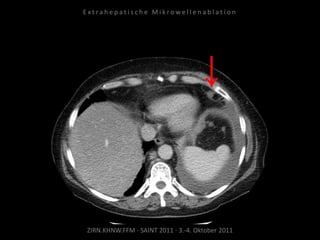

Bildgebung vor MWA:

CT 14.03.2011

Situation:

Nur 1 Metastase, diese ist jedoch

progredient. Kritische Lage in

Herznähe.

Ziel:

Destruktion der solitären Metastase

unter Schonung der Nachbar-

strukturen.

Indikation zur MWA:

Nachweis nur einer Metastase, diese

ist progredient, in der Größe gut zur

Ablation geeignet.

Ablation am 24.03.2010:

2 Nadelpositionen.